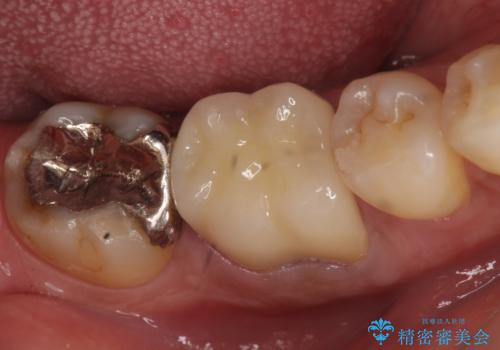

[30代女性]オールセラミッククラウン 根管治療後の補綴

- 右下6番目の歯を他院で治療していたが痛みが引かないため、もう一度根管治療からやり直したいと来院された方の症例です。

再根管治療を行ったところ症状が改善したため、ファイバーコアによる築造及び、オールセラミッククラウン(スタンダード)による補綴を行いました。

- オールセラミッククラウン(スタンダード)…¥100,000、ファイバーコア…¥20,000、仮歯…¥10,000費用は治療当時の料金となります